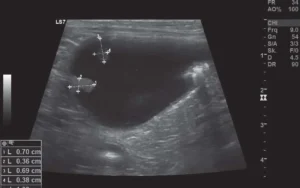

Khi siêu âm thấy các khối lồi ra trong lòng bàng quang, có chân hẹp, đỉnh to, có thể một hoặc nhiều khối — ta nên nghĩ đến polyp hoặc khối u.

Phân biệt nhanh:

Viêm nặng: Dày đều toàn bộ niêm mạc bàng quang, không khu trú.

Polyp / Khối u: Dày khu trú, chỉ ở một vùng, còn vùng khác bình thường.